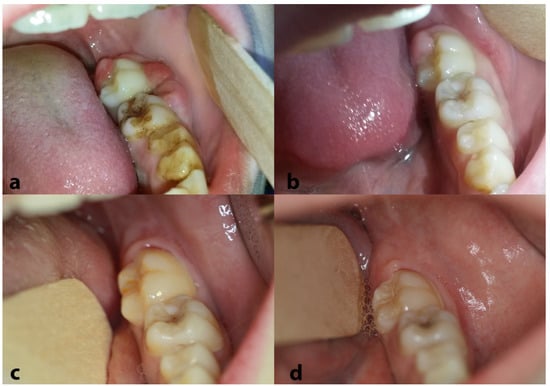

| 44 | Papadopoulou et al., 2024 (present case) | 11 | F | Painful swellings of the gingiva of the lower molars, tooth hypermobility, and facial asymmetry | Bilateral gingival swellings (erythematous and focally ulcerated) adjacent to mandibular premolars and molars that were hypermobile, displaced, and partially extruded Facial swelling along the right posterior mandible | Panoramic radiograph: ill-defined radiolucencies in the posterior mandible bilaterally, ‘floating-in-air’ teeth appearance CT: hypodense masses along and distal to the mandibular ramus extending upwards into the maxillary sinuses bilaterally, and the posterior wall of the right orbit; perforation of the right mandibular cortex | 11 years, no recurrence |